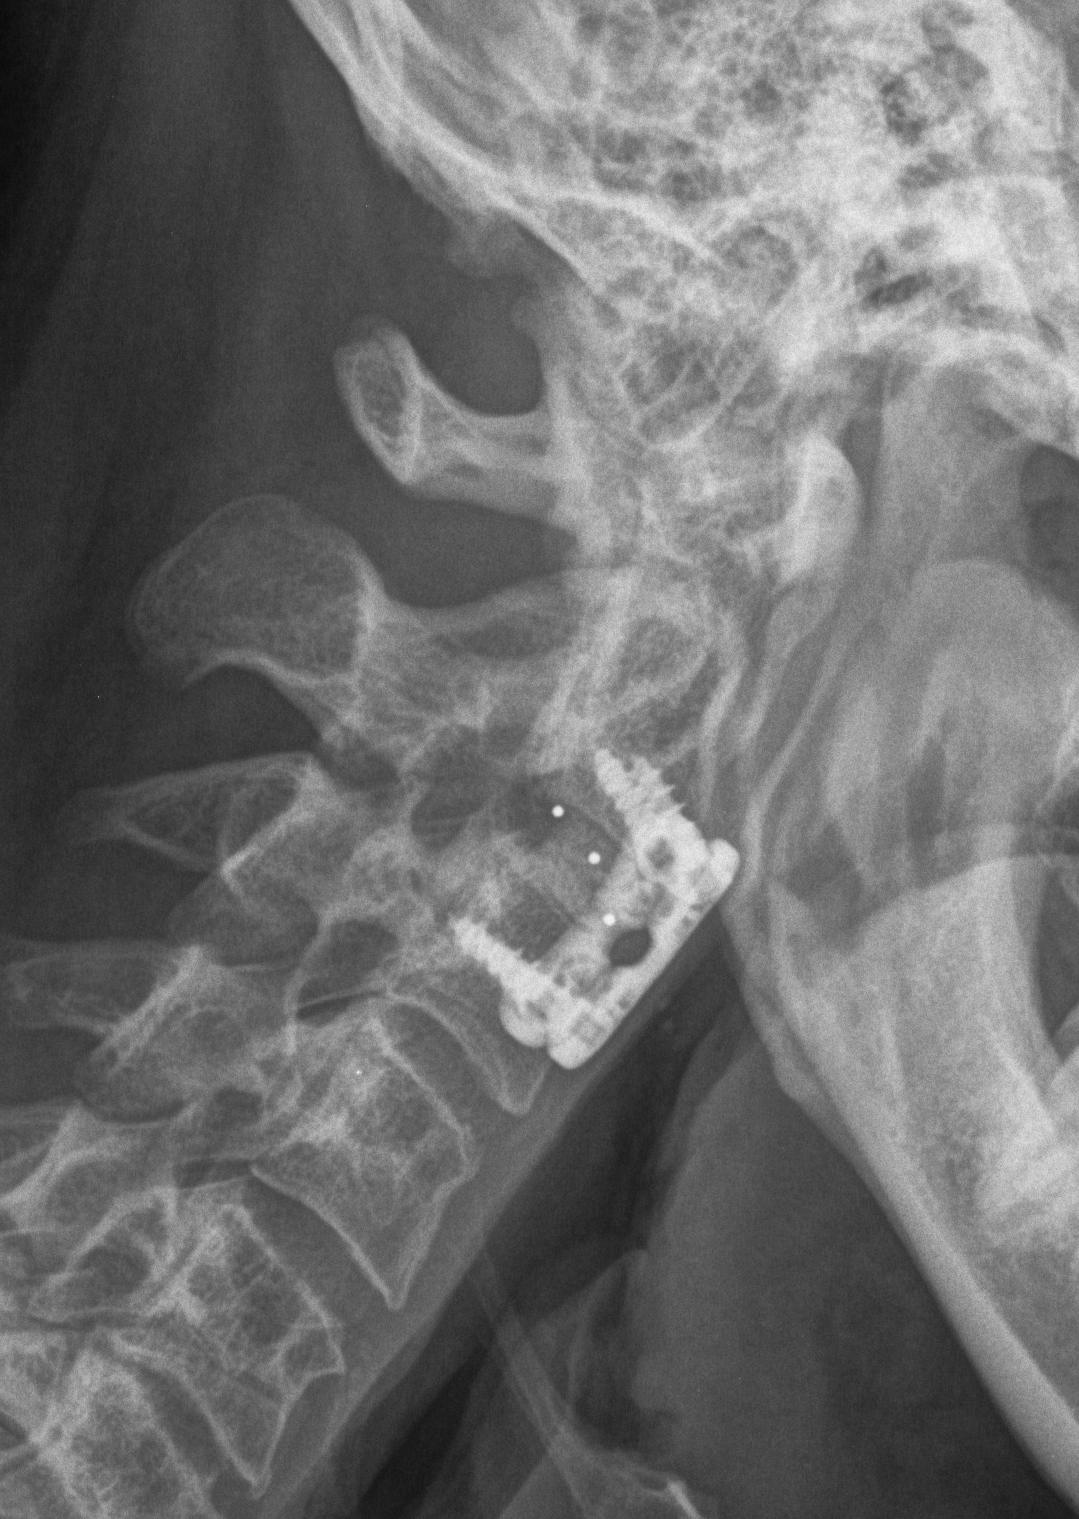

X-ray

Typical changes of spondylosis

- disc space narrowing

- osteophyte formation

- degenerative facet & uncovertebral joints

Severe C5/6 disc degeneration